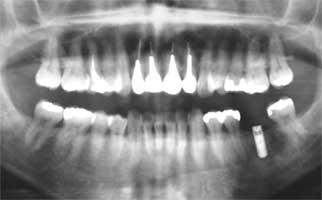

初診時パノラマ

2-|-2初診時

確かにレントゲン的にしっかりした根管充填が為されており、根尖病巣も見あたりません。 但し、押さえて痛い部分が根尖部ではなく、かなり歯頚部寄りですので炎症の原因が歯石を 始めとした汚れだと思います。軽めの歯石除去から始めて経過を見ながら徐々に激しい汚れ の除去を行なうべきだとは思いましたが、遠方からの来院という特殊な事情がありますので、 いきなり手術まがいの処置になってしまいました。一時的には歯磨きもできない程の痛みに なるとは思いますが、多少長めに経過をみておいてください。

14日に受診をして治療をしていただきました。お忙しい中、先生にもスタッフの方にも、 とても親切に診察、説明をしていただき、本当にありがとうございました。とても感謝して います。前の4本について、神経を抜いてから16年以上も経っているのに、根尖病巣もな く、差し歯にも特に問題がないというのは、運がいいとしかいえませんね。差し歯にしてい るから虫歯になる心配はないだろうという気持ちがあり、ケアが不十分だったと自分でも自 覚していたので、汚れが原因だろうといわれて、納得しました。

インプラントの隣、一応有髄歯ですね。確かに歯髄が死んで、根尖部に病巣ができかかった ようにも見えます。しかし、現段階では、疑いだけです。インプラントの隣ですのでたびたび レントゲンを撮る機会も多いと思いますので、明らかな根尖病巣が確認できた段階、もしくは 痛みを感じるようになった段階で根管治療を行なえば良いでしょう。その場合には、姫路まで ご足労いただいた方が早いかも知れません。21|1の根管治療をされた先生が良いかも。